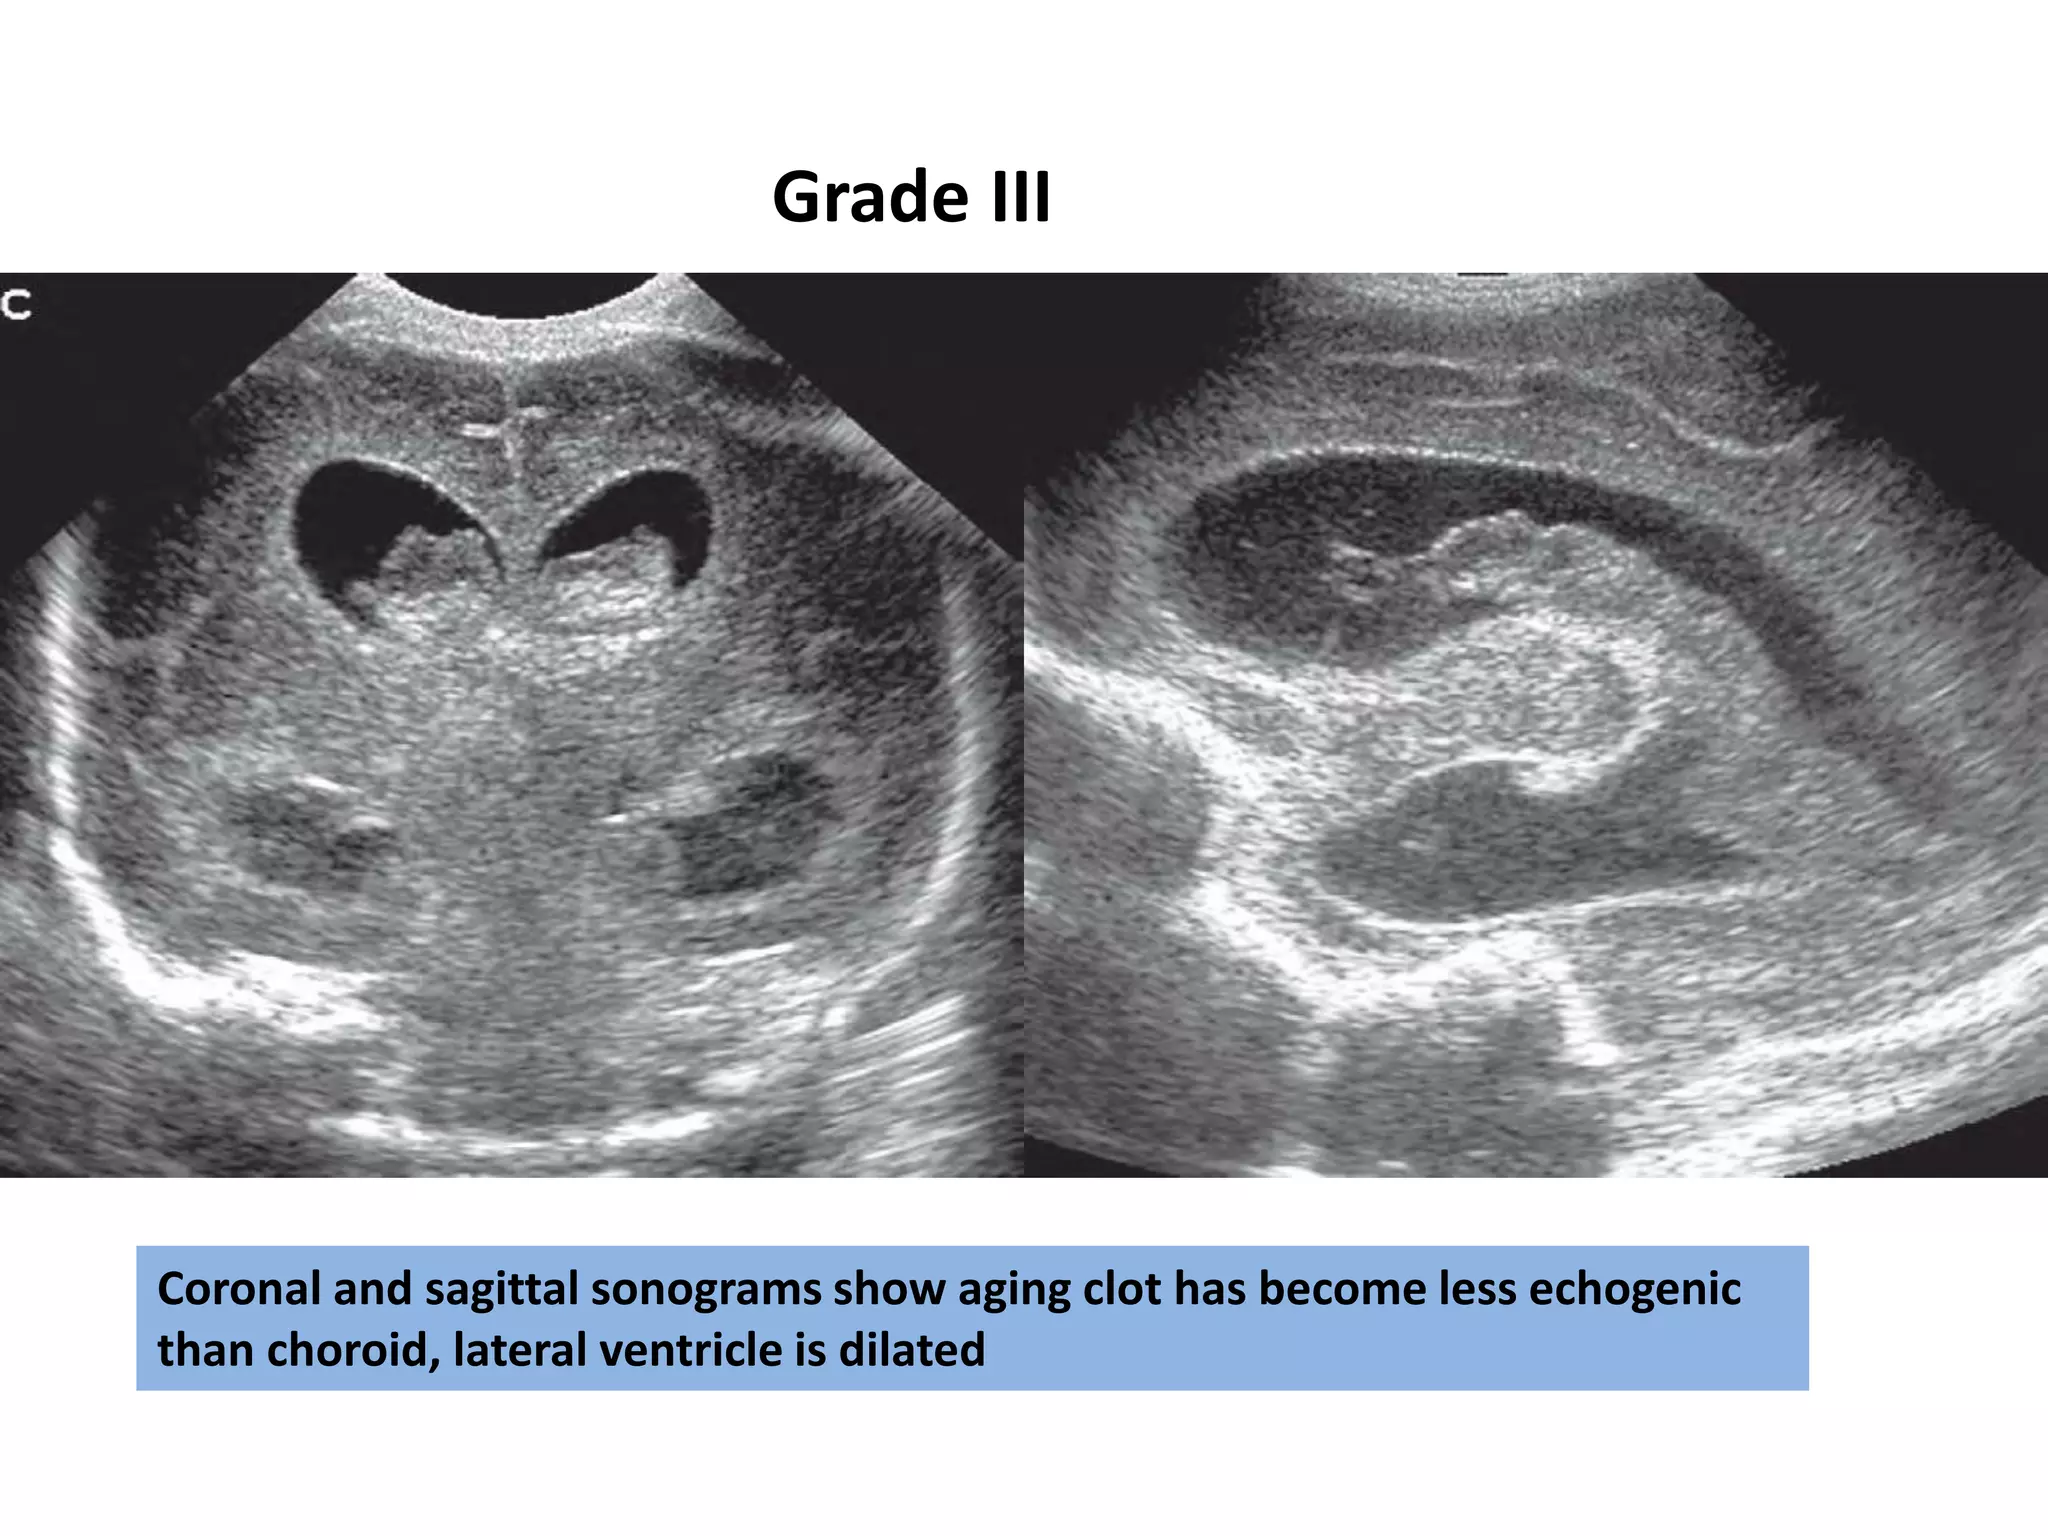

Coronal and sagittal sonograms show aging clot has become less echogenic

than choroid, lateral ventricle is dilated

Grade III

Coronal and sagittalsonograms show aging clot has become less echogenic than choroid, lateral ventricle is dilated Grade III